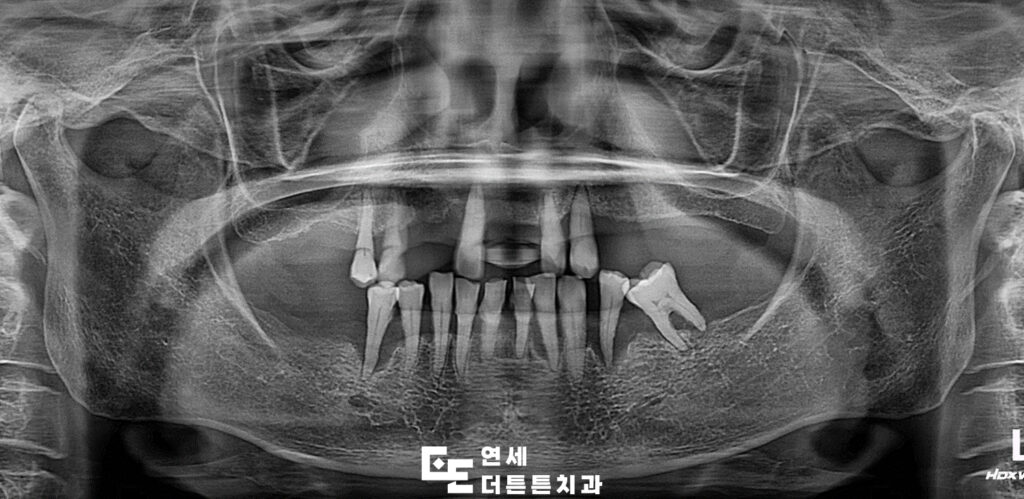

방학역치과에 내원하신 환자분께서는

여러 개의 치아가 이미 상실된 상태였고,

잇몸 염증이 장기간 진행되면서

잇몸뼈가 상당 부분 흡수되어

남아 있는 치아들 역시 흔들림이

나타나고 있는 상황이었습니다.

정밀 검사를 통해 보존이 어려운 치아는 발치를 결정하고

해당 부위에는 임플란트 치료를 계획하였으며,

기능적으로 유지가 가능한 치아는 신경치료 후

크라운 보철로 회복하는 방향으로 치료 계획을 세웠습니다.

자연치가 빠진 뒤 오랜 기간이 지나면

해당 부위를 지지하던 치조골이

점차 줄어드는 현상이 나타날 수 있습니다.

이러한 변화는 이후 임플란트 치료의

난이도에도 영향을 주게 되는데요.